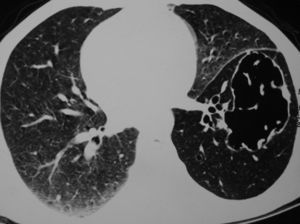

Caso clínicoUn hombre de 45 años de edad solicitó una valoración de su médico de cabecera tras los antecedentes de esputo hemoptoico y tos seca de un mes de duración. Por consiguiente, fue derivado al hospital de los autores después de que la visión posteroanterior de una radiografía de tórax (fig. 1) mostrara la presencia de un quiste en el lóbulo inferior izquierdo (LII). En la valoración inicial se obtuvo una anamnesis en la que el paciente refirió antecedentes de tabaquismo de 26 paquetes/año. También refirió que en la radiografía de tórax previa, efectuada 2 años antes en una revisión médica anual sistemática, no se encontraron anomalías. Tampoco tenía antecedentes de enfermedades respiratorias previas. La exploración física reveló una disminución de la intensidad del murmullo vesicular sobre las áreas inter e infraescapulares internas. La tomografía computarizada (TC) de tórax reveló un quiste de forma irregular y pared fina, junto con una disminución generalizada de la atenuación en el LII (fig. 2). Se programó una broncoscopia de fibra óptica (BFO), pero el paciente se perdió para el seguimiento. Más tarde regresó tras un período de 2 meses, en vista de los síntomas crecientes. Se asociaban con anorexia y una pérdida de peso de 4kg. La TC repetida de tórax (fig. 3) demostró el colapso completo del LII que contenía un quiste lleno de líquido, colapsado (flecha negra). También se observó una masa en la región hiliar izquierda con la pérdida de los planos de grasa en la aorta descendente. En la BFO (vídeo 1) se observó una proliferación en el bronquio principal izquierdo a 4cm de la carina que ocluía por completo el bronquio principal del LII. En la biopsia endobronquial se demostró la presencia de un carcinoma de células escamosas (fig. 4). Más tarde, el paciente recibió 4 ciclos de quimioterapia con docetaxel y cisplatino, seguidos de radioterapia torácica (secuencial) como tratamiento combinado para un cáncer de pulmón no microcítico en estadio IIIB. Más adelante se demostró la progresión de la enfermedad, y falleció alrededor de 10 meses después del diagnóstico.